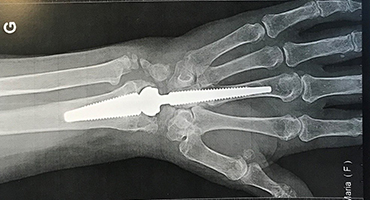

Prothèse de poignet : principe et objectifs

La prothèse de poignet vise à remplacer les surfaces articulaires détruites par un implant artificiel. Contrairement à l’arthrodèse, l’objectif est de conserver une mobilité du poignet tout en supprimant la douleur.

La prothèse permet de préserver une certaine amplitude de mouvement, ce qui peut améliorer le confort dans les gestes du quotidien. Cependant, elle impose des contraintes spécifiques et n’est pas adaptée à tous les patients.

Avantages de la prothèse de poignet

L’avantage principal de la prothèse est la conservation partielle de la mobilité. Les patients peuvent réaliser plus facilement certains gestes nécessitant de la flexion ou de l’extension du poignet.

La douleur est généralement bien soulagée, ce qui améliore la qualité de vie. Pour certains patients, cette solution permet un meilleur confort dans les activités fines et domestiques.